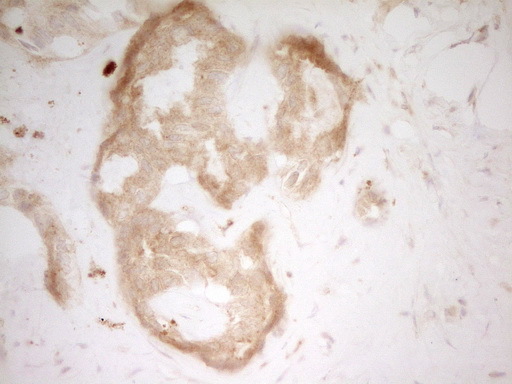

- IHC of paraffin-embedded Human Kidney tissue using anti-TFPI mouse monoclonal antibody. (Heat-induced epitope retrieval by 1 mM EDTA in 10mM Tris, pH8.5, 120°C for 3min).

- Experimental details

- IHC of paraffin-embedded Carcinoma of Human liver tissue using anti-TFPI mouse monoclonal antibody. (Heat-induced epitope retrieval by 1 mM EDTA in 10mM Tris, pH8.5, 120°C for 3min).